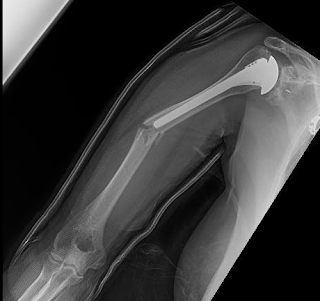

Had a total shoulder arthroplasty 4 years ago

Recently the patient fell, landing on the outstretched arm. At an outside facility, the arm was placed in a plaster splint and x-rays taken with the elbow externally and internally rotated.

The splint was removed and the arm was placed in a sling that aligned the fracture well as revealed by two views shown below taken while the arm was in the sling with the forearm across the abdomen.

We anticipate that this fracture will heal without surgery.

Comment: This case points out that the thorax is often the best splint for a midshaft humeral fracture. It also shows that x-ray views of a fractured arm with the distal humerus internally and externally rotated may not be a good idea.